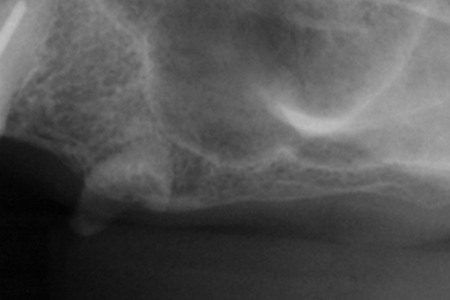

抜歯を伴う症例。抜歯後の病巣に対する処置が、インプラントの成功の決め手となります。